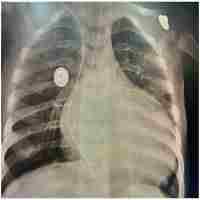

| Abstract | Vertical transmission of SARS-CoV-2 from mother to fetus is widely accepted. Whereas most infected neonates present with mild symptoms or are asymptomatic, respiratory distress syndrome (RDS) and abnormal lung images are significantly more frequent in COVID-19 positive neonates than in non-infected newborns. Fatality is rare and discordant meta-analyses of case reports and series relating perinatal maternal COVID-19 status to neonatal disease severity complicate their extrapolation as prognostic indicators. A larger database of detailed case reports from more extreme cases will be required to establish therapeutic guidelines and allow informed decision making. Here we report an unusual case of a 28 weeks' gestation infant with perinatally acquired SARS-CoV-2, who developed severe protracted respiratory failure. Despite intensive care from birth with first line anti-viral and anti-inflammatory therapy, respiratory failure persisted, and death ensued at 5 months. Lung histopathology showed severe diffuse bronchopneumonia, and heart and lung immunohistochemistry confirmed macrophage infiltration, platelet activation and neutrophil extracellular trap formation consistent with late multisystem inflammation. To our knowledge, this is the first report of SARS CoV-2 pulmonary hyperinflammation in a preterm newborn with fatal outcome. |